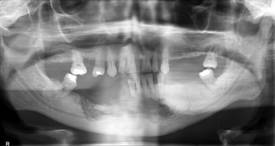

Por otro lado, el estudio panorámico proporcionó una imagen radiolúcida correspondiente a destrucción ósea, que se extendía desde la cara lateral de la mandíbula en la cara mesial del diente 47 hasta el sector anterior de la mandíbula, dejando sin soporte al 41 (fig. 1). La zona ósea afectada se prolongaba por debajo de los dientes anteroinferiores restantes, aunque estos no presentaban movilidad.